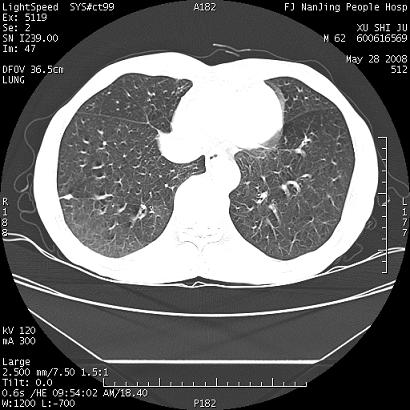

以下是引用杀毒软件在2008-5-28 19:16:00的发言:[br]病灶旁“晕轮征”,考虑肺真菌病

以下是引用qiushi在2008-5-28 20:01:00的发言:[br]空洞周围环状磨玻璃影(日晕征),考虑肺曲霉菌病.

以下是引用yuhongjun在2008-5-29 4:28:00的发言:[br]空洞周围环状磨玻璃影(日晕征),考虑肺曲霉菌病。支持! [br] [br]

以下是引用lrj在2008-5-28 21:10:00的发言:[br]所示应该是正常结构,是对称的,多个层面都有!也不像是内乳动脉或是肿大淋巴结![br]右下肺渗出性病变伴空洞形成,其洞内见一结节,以下诊断都有可能:1 右下肺曲菌感染, 2右下肺结核空洞形成伴曲菌感染!3右下肺结核空洞伴壁内占位形成,虽说后者发生的几率很低 但作为我们应该多考虑一下吧!最重要的结合临床